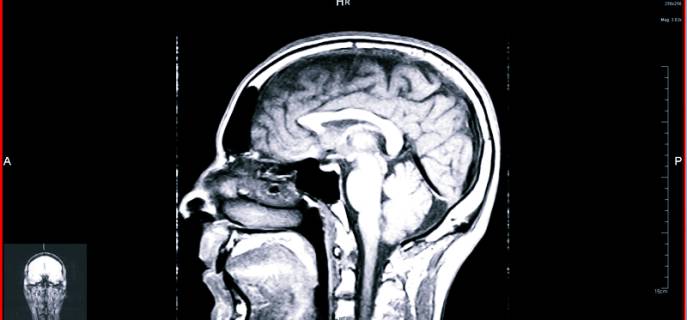

Магнитно-резонансная томография

Не зря в зарубежных фильмах о работе медицинских учреждений врачи постоянно направляют больных на МРТ – сегодня она находится в лидерах среди методов исследования головного мозга. Визуализация состояния органа происходит благодаря магнитному полю, постоянно поддерживаемому в томографе. Через него пропускают электромагнитные волны, энергетический поток от которых отбивают атомы водорода, присутствующего во всех клетках человеческого тела. Компьютерное оборудование преобразовывает полученные данные в снимки тканей мозга.

МРТ эффективна для диагностирования широкого спектра заболеваний: от патологий сосудов до опухолей.

Современные томографы излучают электромагнитные поля низких частот и комплектуются целым рядом специализированных компьютерных программ, что позволяет получить детальную картину функционирования мозга.

Как и при КТ, для обследования человек должен лечь на подвижный стол, где его тело будет закреплено специальными ремнями, а к голове присоединены сенсорные датчики, посылающие и считывающие сигнал. После стол перемещается в томограф. В зависимости от количества программ, задействованных для сканирования, длительность процедуры составляет 15-40 минут. Все это время человек должен лежать неподвижно.